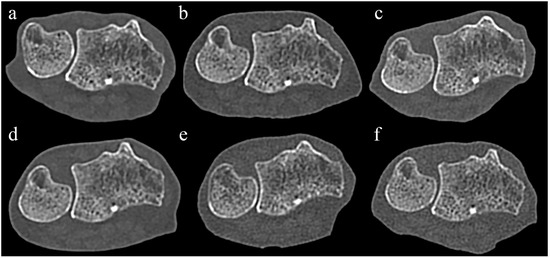

Figure 5 compares Sn−, Sn+, and VMI images from PCCT and two representative EIDCTs (Drive and Force). Images from all scanners are provided in Figure S1.

Figure 5. Comparison of PCCT and two representative dual-energy EIDCT images containing metal artifacts. Images were obtained by using Alpha (panels (ac)), Drive (panels (df)), and Force (panels (gi)) scanners. The left column shows images obtained without tin filtration (Sn−), the middle column shows images obtained with tin filtration (Sn+), and the right column shows 120 keV virtual monoenergetic images (VMIs).

Although there were no significant differences in both subjective scores (overall metal artifacts and adjacent tissue visibility) among Sn− images, overall metal artifact severity in PCCT exhibited a trend toward higher scores than EIDCTs (Table 8). For Sn+ images and VMIs, no statistically significant differences in both subjective scores were observed between PCCT and EIDCTs. Inter-reader agreement among three interpreters was 0.92 (95% CI, 0.79–0.98; p < 0.001) for scores of overall metal artifacts and 0.82 (95% CI, 0.21–0.95, p < 0.001) for adjacent tissue visibility

3.5. Quantitative Results of the Third Session

For PCCT, the areas of streak artifacts significantly decreased in the following order: Sn− > Sn+ > VMI (p < 0.001). The streak artifact areas for PCCT were significantly larger than those for EIDCT, both in Sn− images (p < 0.001) and Sn+ images (p < 0.001). However, the areas of streak artifacts in VMIs generated using PCCT were significantly smaller than those produced using three dual-energy EIDCT scanners (p < 0.001 or 0.001; Figure 6).